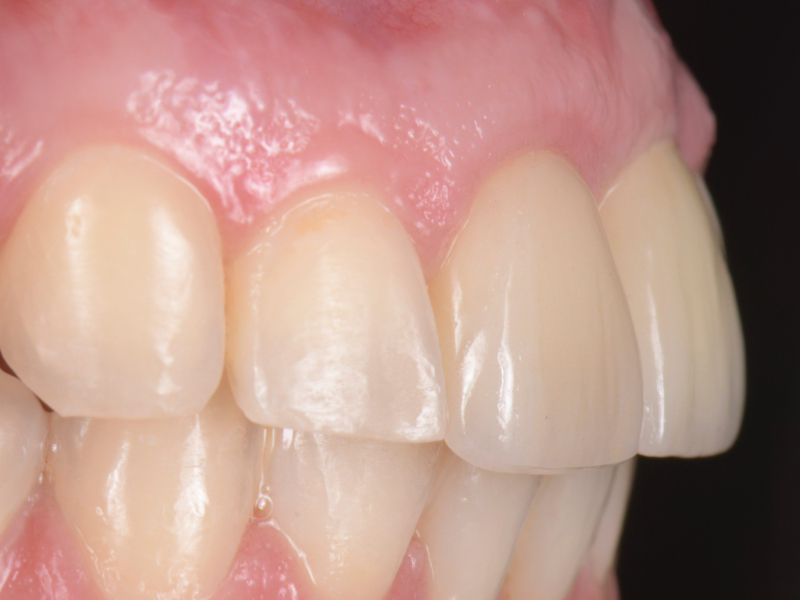

The esthetic success of an anterior implant-supported restoration mostly depends on having a soft-tissue architecture indistinguishable from the adjacent teeth. One of the most critical steps to achieve this “esthetic success” is correctly using the provisional restoration to optimize and properly contour (groom) the peri-implant tissue anatomy.

Once the optimal emergence profile has been developed, we need to communicate and transfer this information properly to the laboratory. Unfortunately, all implant companies provide stock round impression copings that do not precisely transfer the soft-tissue contours. A simple protocol to communicate this information is described here.

This visual essay walks through a step-by-step description of how to fabricate a personalized impression coping with transfer ofthe peri-implant tissue anatomy properly.